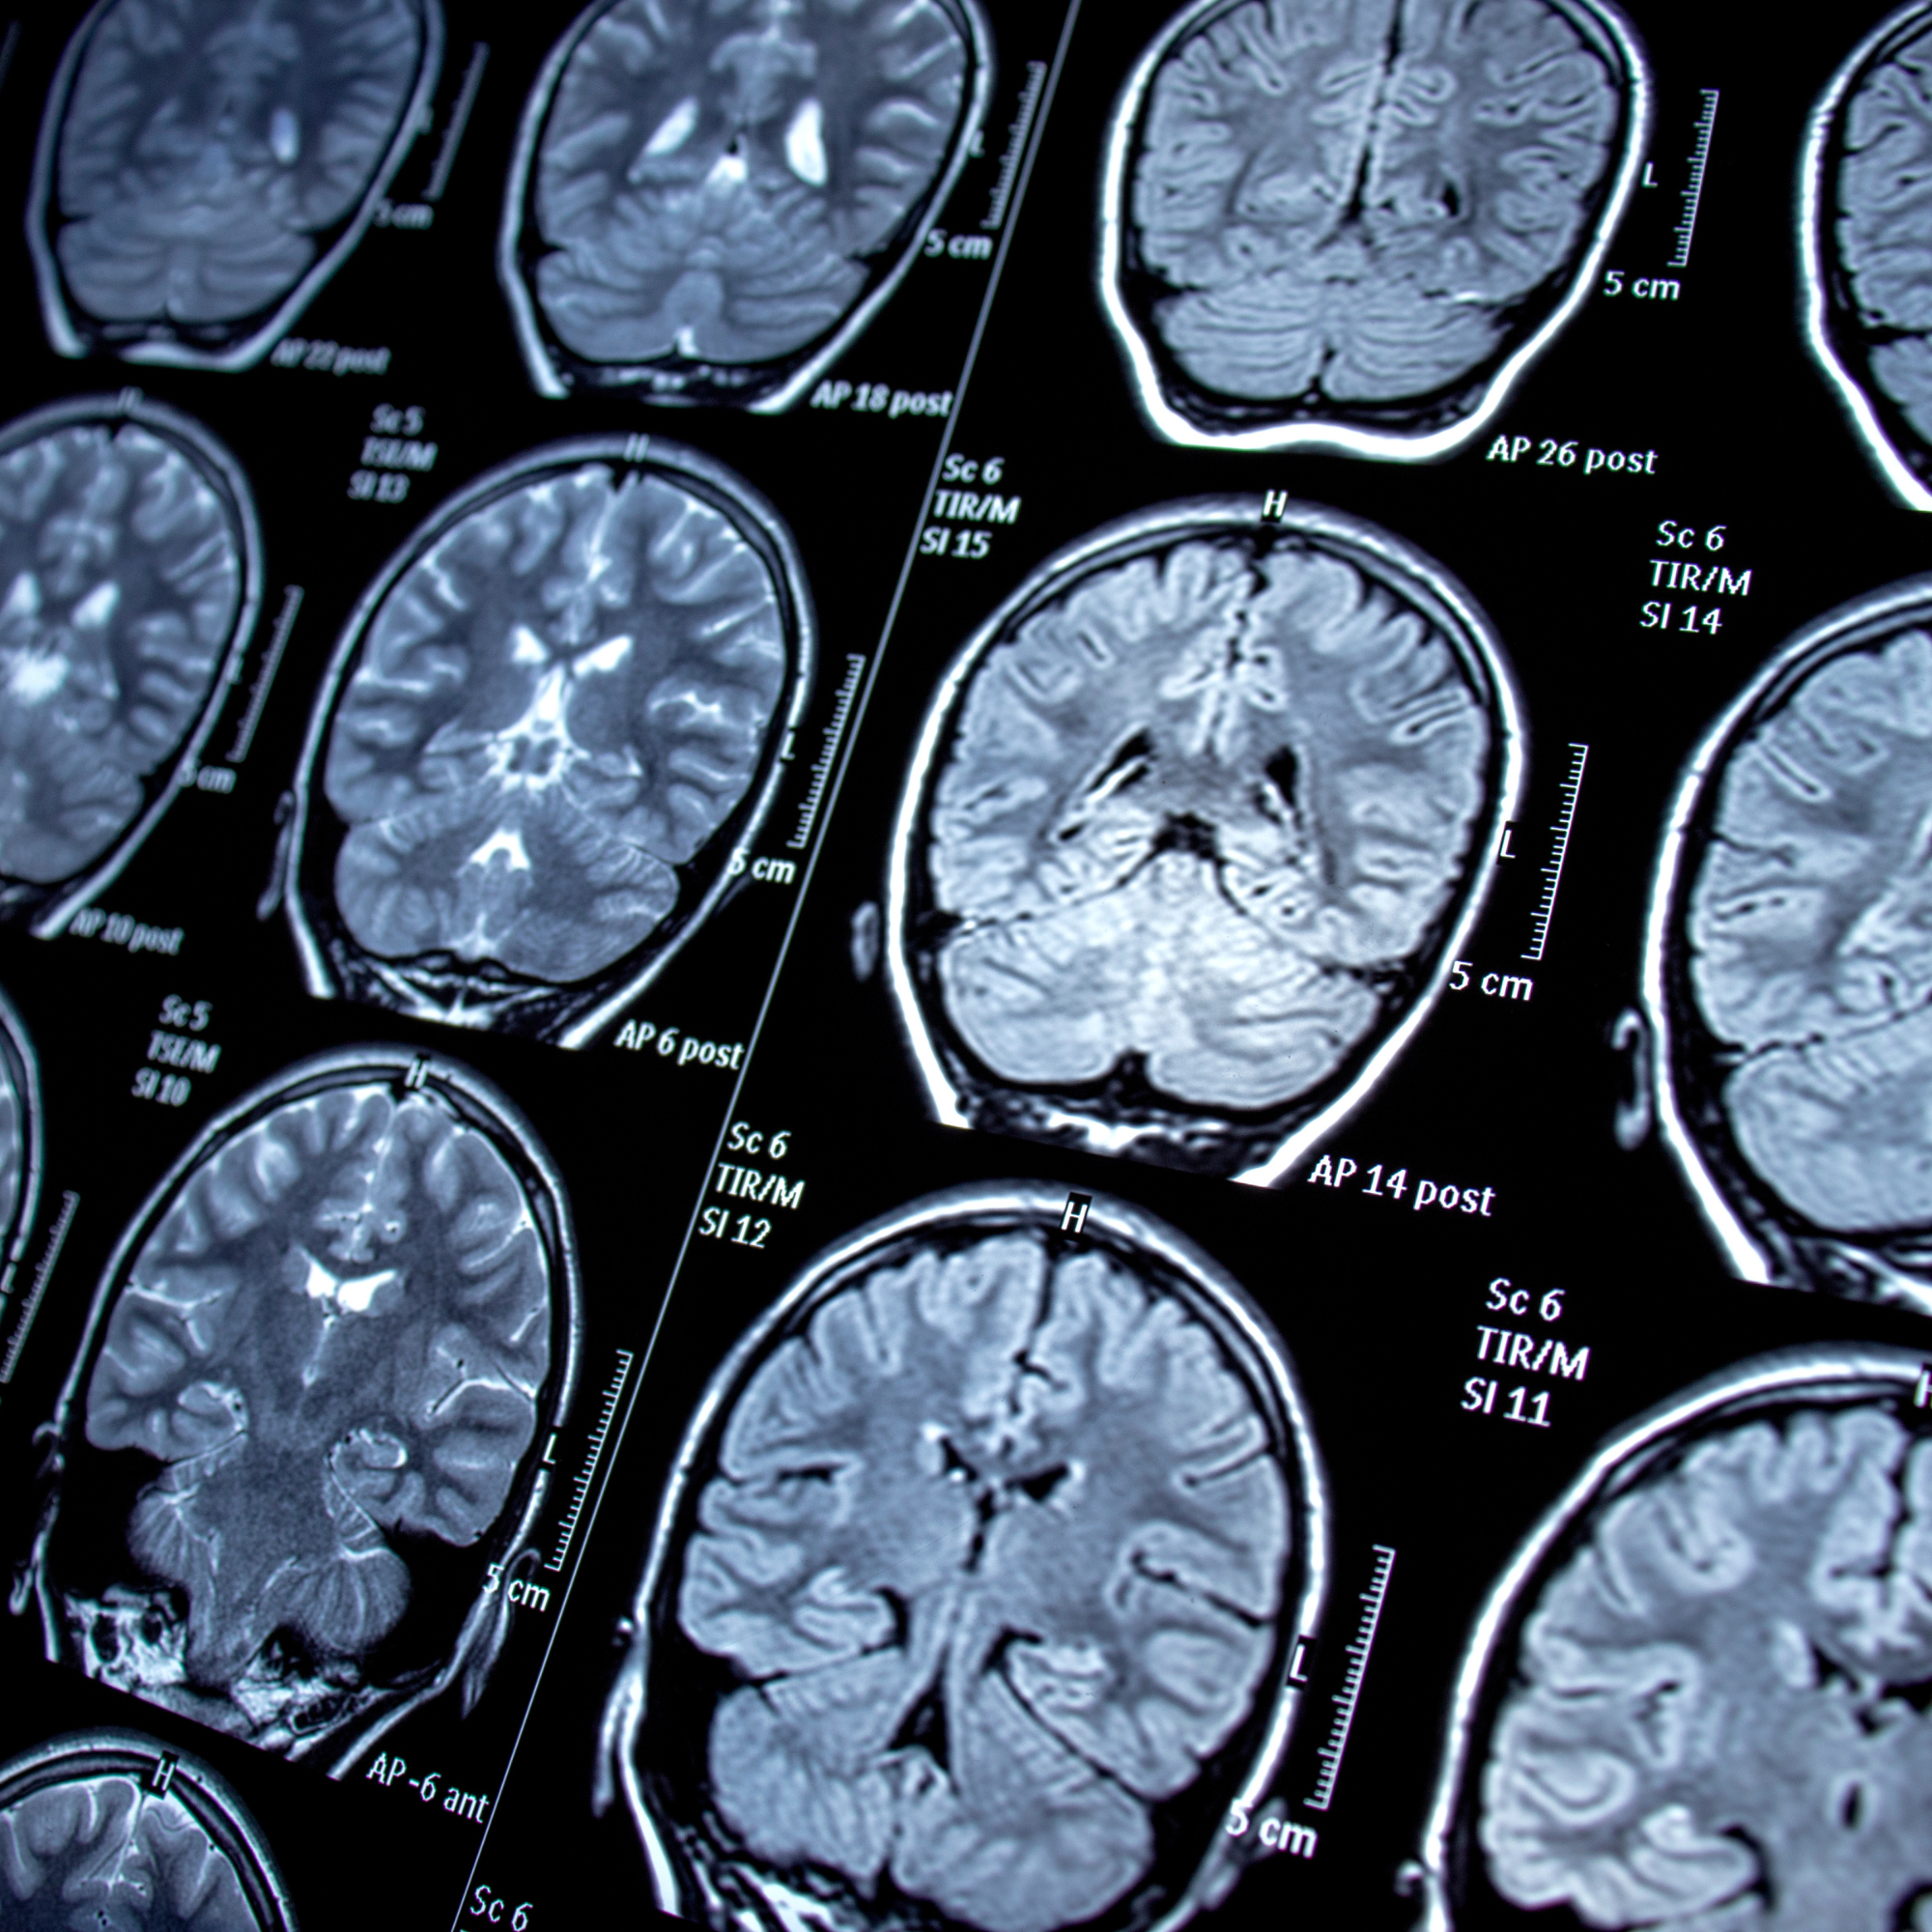

L’imagerie par résonance magnétique

L’imagerie par résonance magnétique

IRM

Imagerie par résonance magnétique chez le chien (ou IRM) : examen d’imagerie qui consiste à soumettre une partie du corps à un champ électromagnétique et à enregistrer les signaux émis en retour.